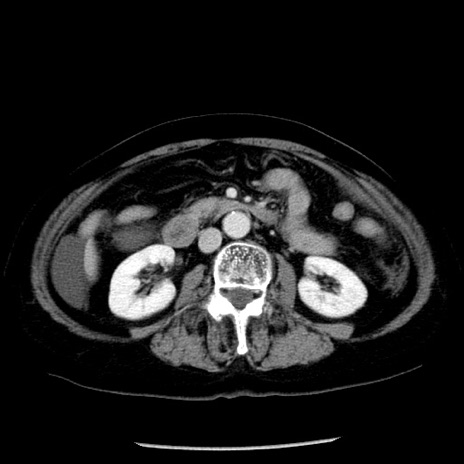

症例13(横断像)

【症例】70歳代女性

【主訴】腹痛、嘔吐

【現病歴】15時間程前(昨晩)より腹痛あり。今朝になっても症状の改善なく、嘔吐あり。腹痛も増悪あり、救急外来受診。

【既往歴】子宮癌全摘術後

【身体所見】意識清明、BP 121/72mmHg、P 74bpm、SpO2 100%(RA)、腹部:平坦・軟、腸雑音ほぼ聴取せず。下腹部・心窩部・臍左上に圧痛あり。反跳痛なし。

【データ】WBC 10600、CRP 0.15